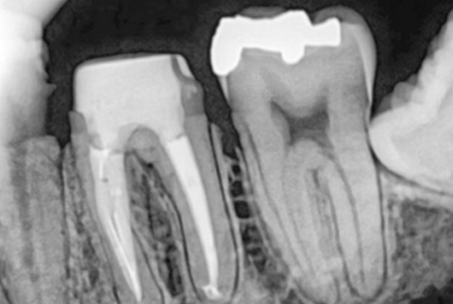

The images above show actual cases treated at SMILE FACE DENTAL CLINIC.

To a non-specialist, they may appear to be ordinary X-rays, but dentists can instantly recognize them.

They can appreciate both the complexity of the treatment and the care and precision involved.